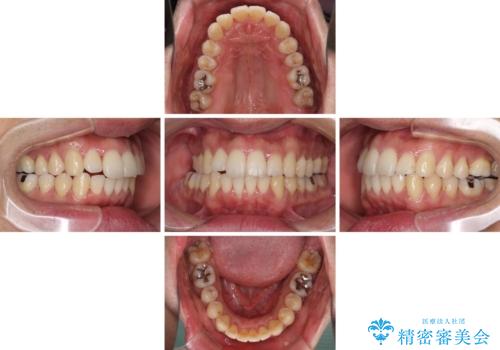

インビザラインは1日22時間を目標にマウスピースを装着することで歯列を改善するものです。

そのため、上下の歯が接触することはほとんどなく、マウスピースを介した咬合において歯列矯正が進んでいきます。

この方は元々骨格的な偏位が大きかったためか、治療中に下顎骨が上顎骨よりも右外側に誘導されて、右側の奥歯が全く咬合しない状態が続いてしまいました。

最終的にはゴムかけなどを活用して改善することができましたが、4年近い治療期間を要することとなりました。